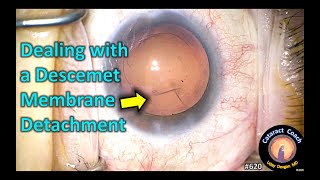

Descemet's Membrane Detachment(DMD) prevention and management video

Descemet's Membrane Detachment(DMD) prevention and management

Descemet membrane detachment (DMD) during stromal hydration DESMETOPEXY | Descemet’s Membrane Detachment | How to manage

DESMETOPEXY | Descemet’s Membrane Detachment | How to manage Management of Descemet membrane detachment - Dr Prafullla Kumar Maharana

Inferior Descemet's Membrane Detachment (DMD) Management. Dr. Deepak Megur Descemet Membrane Detachment during Cataract Surgery

Descemet Membrane Detachment during Cataract Surgery Descemet's membrane detachment (DMD)

Descemet's Membrane Detachment(DMD) prevention and management

Descemet membrane detachment (DMD) during stromal hydration DESMETOPEXY | Descemet’s Membrane Detachment | How to manage

DESMETOPEXY | Descemet’s Membrane Detachment | How to manage Management of Descemet membrane detachment - Dr Prafullla Kumar Maharana

Inferior Descemet's Membrane Detachment (DMD) Management. Dr. Deepak Megur Descemet Membrane Detachment during Cataract Surgery

Descemet Membrane Detachment during Cataract Surgery Descemet's membrane detachment (DMD)